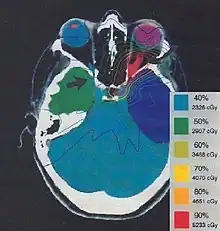

The more formal optimization process is typically referred to as forward planning and inverse planning.[12][13] Plans are often assessed with the aid of dose-volume histograms, allowing the clinician to evaluate the uniformity of the dose to the diseased tissue (tumor) and sparing of healthy structures.